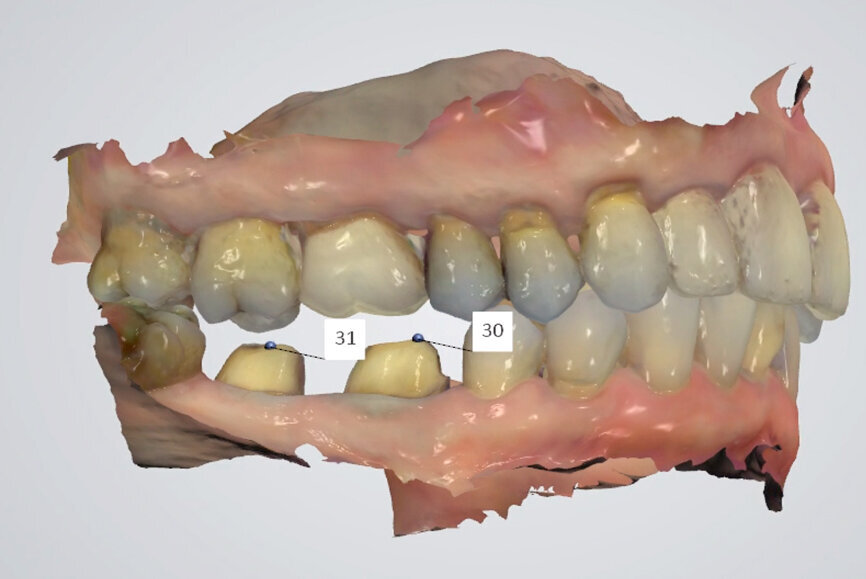

Fig. 16: Occlusion with intercuspation but a non-functional

mandibular position.

Fig. 17: Treatment modalities to recreate intercuspation in the new mandibular position.

Fig. 18: TRIOS 3 software (3Shape) matching digital casts of arches to side view inter-arch scan (in light blue).